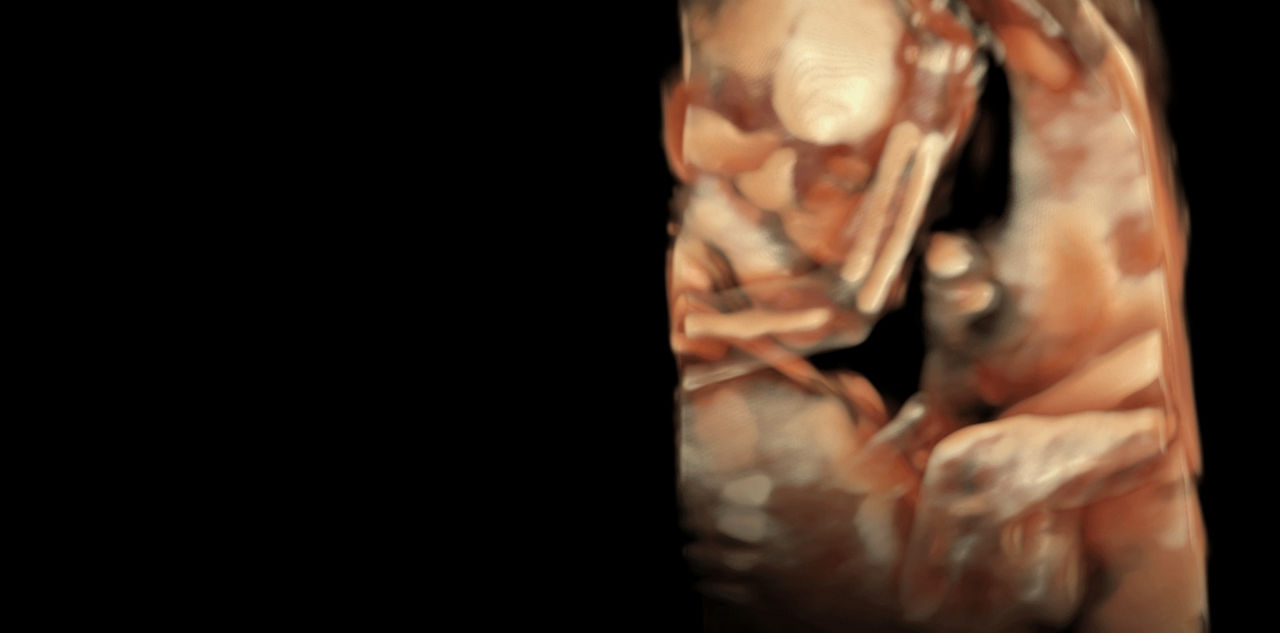

Generate spectacular 2D/3D and color Doppler images with increased penetration and stunning clarity, to help visualize critical details needed for diagnostic assurance. The Lyric Architecture unlocks new imaging and processing power to expand your imaging capabilities for years to come